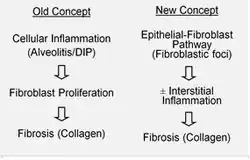

Se cree que la FPI es el resultado de un proceso de cicatrización aberrante que incluye o afecta a un depósito anómalo y excesivo de colágeno (fibrosis) en el intersticio pulmonar con una inflamación mínima asociada.[13]

La hipótesis actual es que la lesión inicial o repetida que ocurre en la FPI afecta a las células pulmonares llamadas epiteliocitos alveolares (EA), que recubren la mayoría de la superficie alveolar.[14] Cuando se dañan o pierden EA de tipo I, se cree que EA de tipo II inician una proliferación para cubrir las membranas basales que han quedado expuestas. En condiciones de reparación normal, el EA de tipo II hiperplástico muere y las células restantes se extienden y experimentan un proceso de diferenciación para convertirse en EA de tipo I. En procesos patológicos y en presencia del factor de crecimiento transformante beta (TGFβ), los fibroblastos se acumulan en estas zonas de daño y se diferencian en miofibroblastos que segregan colágeno y otras proteínas.[14] Anteriormente se pensaba que la inflamación era el proceso inicial de la cicatrización del tejido pulmonar. Sin embargo, de acuerdo con los hallazgos más recientes, el desarrollo de los focos fibroblásticos antecede a la acumulación de células inflamatorias y el posterior depósito de colágeno.[15]